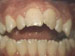

Underbite: Lower front teeth in front of uppers